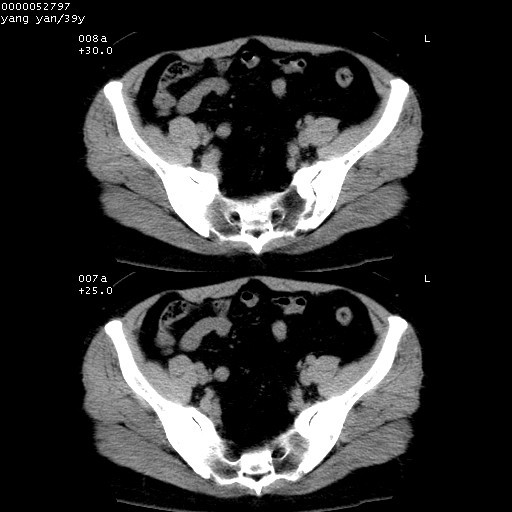

患者 女,39岁。因外伤检查,偶然发现。

典型!双侧骶髂关节致密性骨炎。

典型!病变主要累及双侧髂骨。常见于育龄期妇女。

致密性骨炎,一般不跨越关节面,可是这个骶骨关节面也有硬化。

髂骨致密性骨炎系一种以骨质硬化为特点的非特异性炎症,有高度致密的骨硬化现象,尤其以髂骨下2/3更为明显,但关节间隙则无改变。因位于骶髂关节,且该关节症状明显,故又称之为“骶髂关节致密性骨炎”。 本病90%以上为中年女性,以妊娠后期、尤其分娩后为多见,亦可见于尿路或女性附件慢性感染后,或盆腔内其他感染。此外,臀骶部的外伤亦可诱发或引起本病。  妊娠、分娩及外伤均可引起骶髂关节韧带的撕裂而易使局部的血供受阻。因此早期局部呈现充血、水肿及渗出增加等,渐而局部出现增生与变性反应,随着胶原纤维的致密化而向硬化演变;血管形成厚壁血管,易闭塞而引起髂骨耳状面处缺血和缺氧,骨质呈现硬化性改变,以致手术时局部出血较少。骶髂关节囊壁显示纤维增生、弹性降低及松动样改变。继发于盆腔内炎症者亦出现相类似的病理改变,可能系细菌内毒素作用所致。